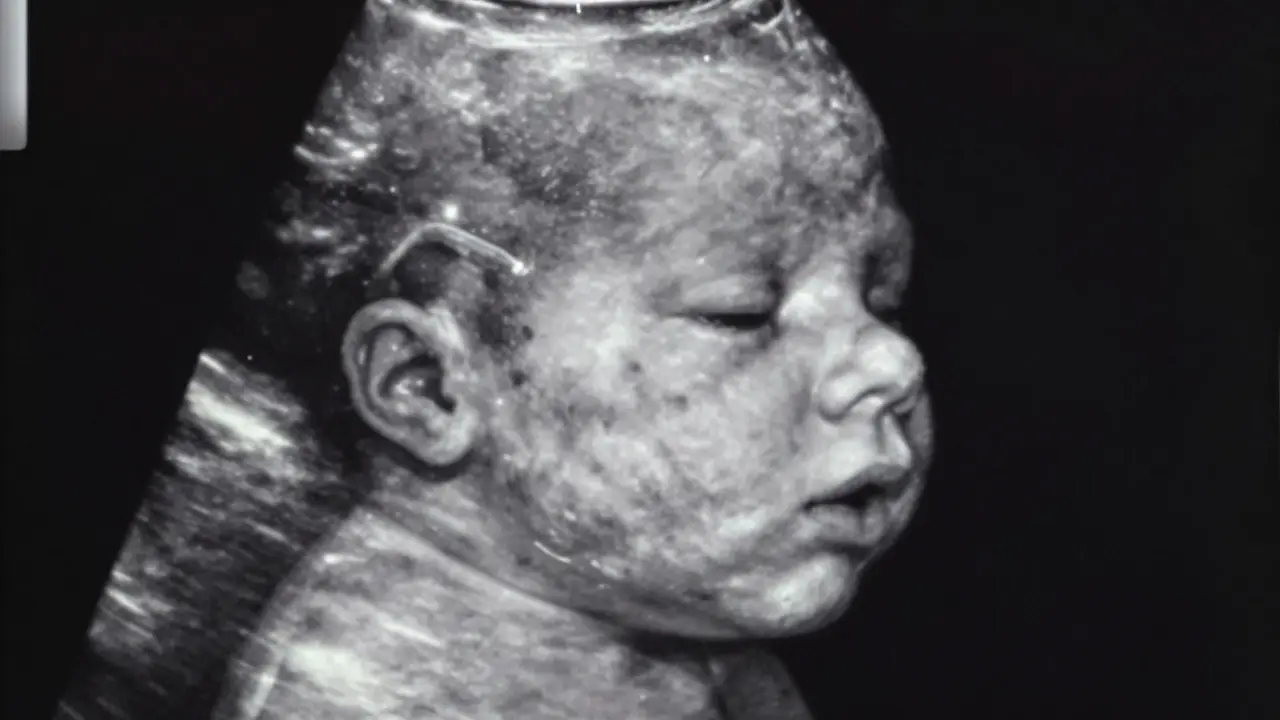

Kdy je vidět srdíčko při ultrazvuku těhotenství

Článek vysvětluje, kdy je možné vidět srdeční tep embrya během ultrazvuku během těhotenství, jaké faktory ovlivňují viditelnost, a poskytuje praktické rady pro budoucí maminky. Uvádí též důležitost sledování srdečního tepu pro zdraví embryo a klid budoucích rodičů. Dále se zaměřuje na to, co znamená viditelný srdeční tep a kdy je vhodné ultrazvuk opakovat.